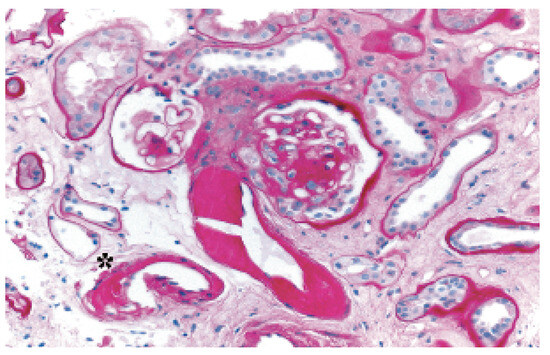

Successful Follow-Up Twenty Years After Heart Transplantation

by Augusto Gallino, Marcello Di Valentino, Claudio Marone, Ludwig von Segesser, Michele Genoni, Tiziano Moccetti, Roberto Corti, Georg Noll, Michael Mihatsch, Christian Seemayer, Kurt Schneider and Marko Turina

Abstract

On September 23rd, 1985, a 34-year-old man with end-stage dilated cardiomyopathy of unknown origin and with history of severe dyspnea (NYHA III–IV) during the preceding five years underwent orthotopic heart transplantation (HTX) [...] Full article

Figure 1